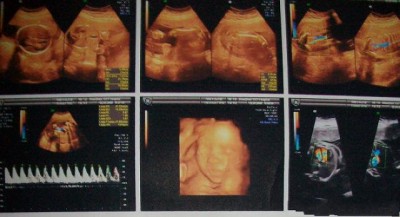

现在胎宝宝身长16~18厘米,重300~500克。这时期,胎儿的体重开始大幅增加,眉毛和眼脸清晰可见,手指和脚趾也开始长出指甲。如果胎儿是个女孩,她的阴道现在已经形成了,并且会继续发育到出生;如果是男孩,*丸睾**将从盆骨降到阴囊内,原始精子已经形成。随着大脑和神经末梢的发育,胎儿的各种感官正在逐步完善,如味蕾开始在舌面上形成。

本周胎儿重350克左右,身长达到了19厘米左右。胎宝宝的脑部开始迅速生长,尤其是位于大脑中心的生发基质,它负责产生脑细胞。胎儿现在看上去滑溜溜的,胎脂覆盖了他的全身。胎脂可以保护胎儿的皮肤,不少胎儿在出生时身上都还残留着这些白色的胎脂。宝宝清醒的时间越来越长,当他清醒时,能够很清楚地听到外面大人的谈话、音乐或噪音。有时孕妈妈轻轻拍打腹部时,他也会被惊醒。

本周胎儿大约重450克,从头到臀长20厘米左右。这时期,胎儿的皮肤薄薄的,红红的,还皱巴巴的,样子像个小老头,但身体比例已经较为匀称。胎儿的嘴唇、眉毛和眼睫毛已清晰可见。宝宝的眼睛已经发育,视网膜也已形成,具备了微弱的视觉。宝宝的嘴唇越来越清晰,在胎儿的牙龈下面,幼小的牙蕾也开始发育了,显露出长牙的最初迹象。

怀孕第24周

本周胎儿身长25-30厘米,体重大约在550克,胎儿的呼吸系统正在发育,不停吞咽羊水来练习呼吸,使肺得到进一步完善。此时宝宝的听力完全形成,他能分辨出孕妈妈发出的说话声音。当然,外界的噪音,如汽车鸣笛、吸尘器等声音也会让胎儿焦躁不安。胎儿在发育身体的同时,也逐步变为有意识的、对感觉有反应的人了,他的外貌和举止已经像出生时的新生儿了。